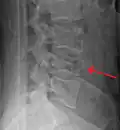

A burst fracture of L4 as seen on CT -

A burst fracture of L4 as seen on CT